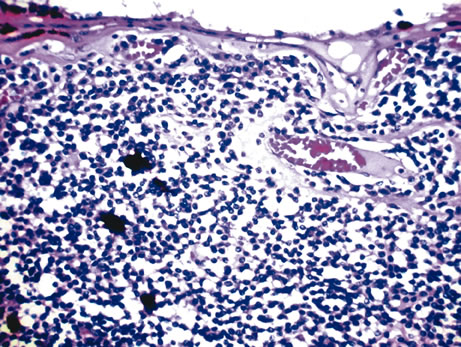

In leukemia, rarely nodular or milky lesions may be present. Histologically, the nodules reveal infiltration of abnormal lymphoid (Fig. 5) or myeloid cells and iris architecture is lost. As the lesion becomes thickened, a pseudohypopyon is common.42 In cases of retinoblastoma, white foci on the anterior iris surface may appear and a pseudohypopyon may also be present.43 Histologically, these foci show abnormal, hyperchromatic, round cells with scant cytoplasm as well as frequent abnormal mitotic figures. Adenomas of the pigmented iris epithelium and adenomas of nonpigmented or pigmented ciliary epithelium may present with nodular lesions pushing the iris stroma. These benign tumors rarely enlarge, seldom undergo malignant transformation, and consist of proliferations of the iris or ciliary body epithelium. Other rare tumors include neonatal hemangiomatosis, and this entity shows multiple vascular spaces that contain erythrocytes and are lined by endothelium (Fig. 6).

Fig. 5. Lymphoma of the iris. Iris stroma is infiltrated by monomorphic-appearing lymphoid cells. The tumor cells were positive for T-cell marker CD3. (Hemotoxylin-eosin ×60.)